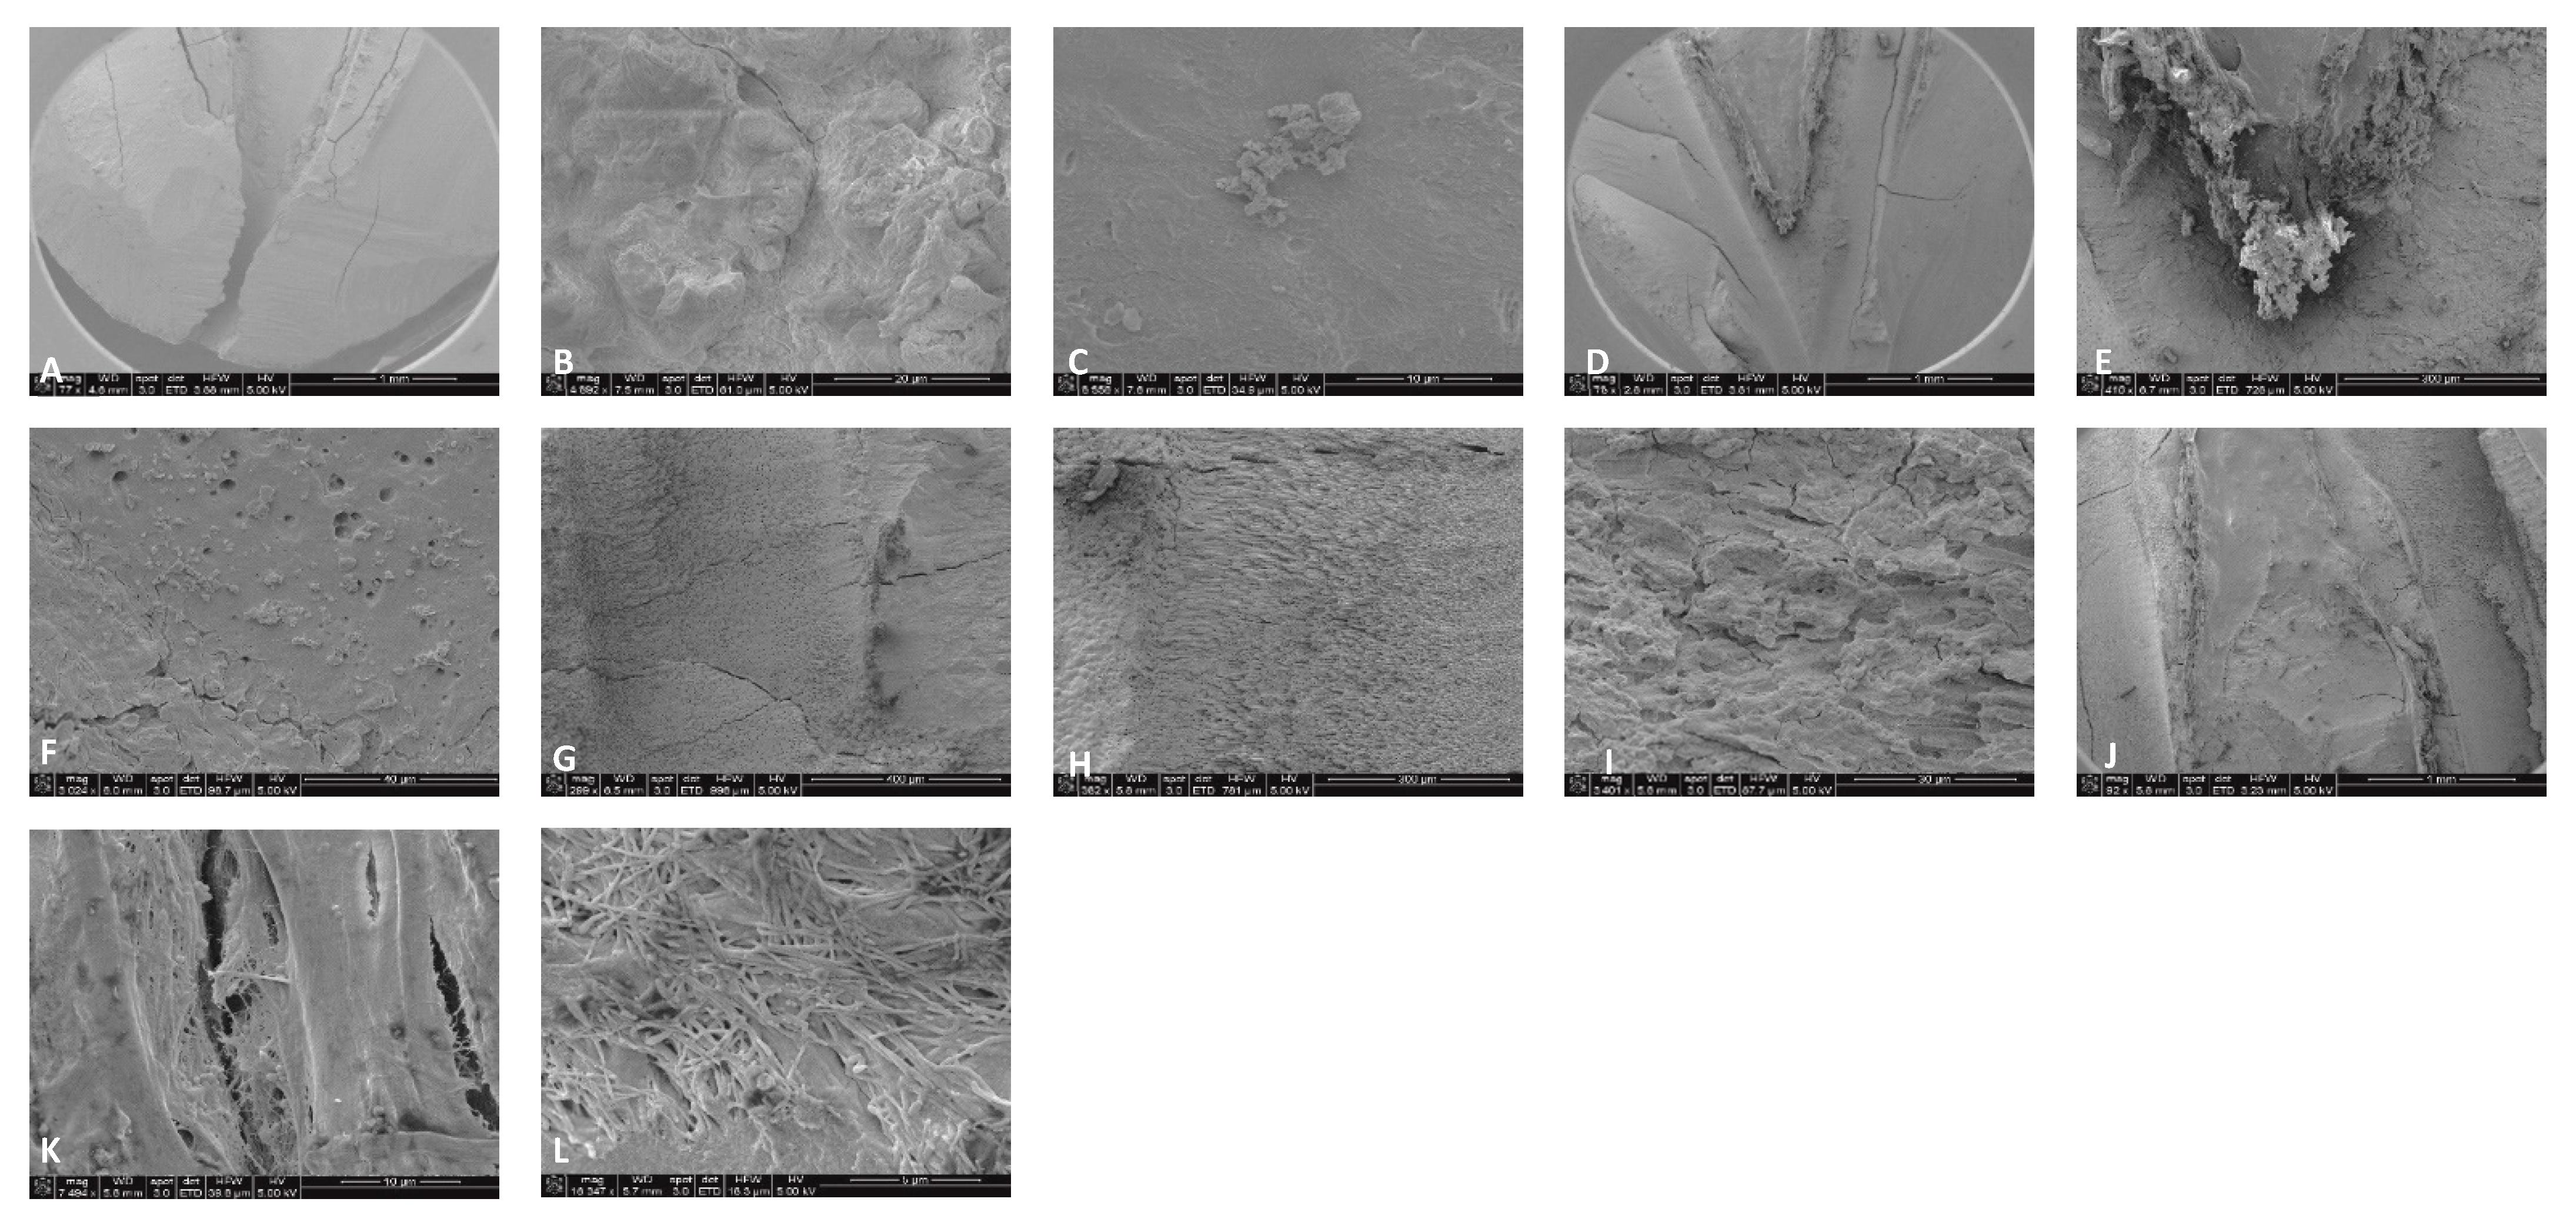

3.3. Scanning Electron Microscopy (SEM)

4.2. SEM Analyses